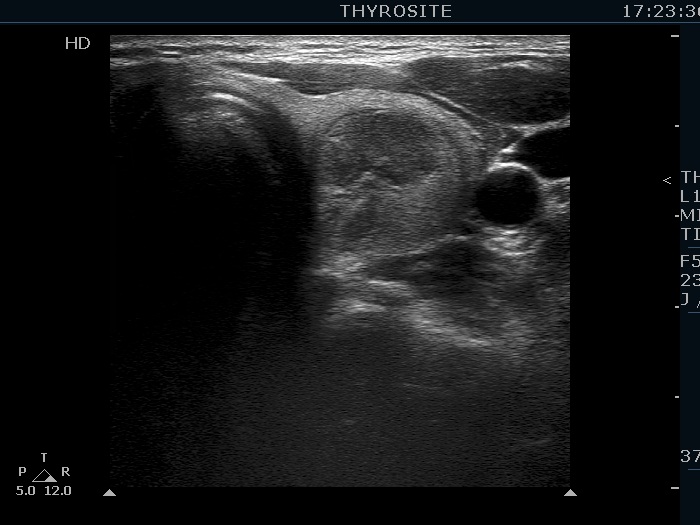

The composition of the nodule - case 956 (ultrasonographic picture 1)

Upper part of the left lobe, transverse scan. There is heterogeneous, partly echonormal, partly moderately hypoechogenic nodule which presents halo sign.